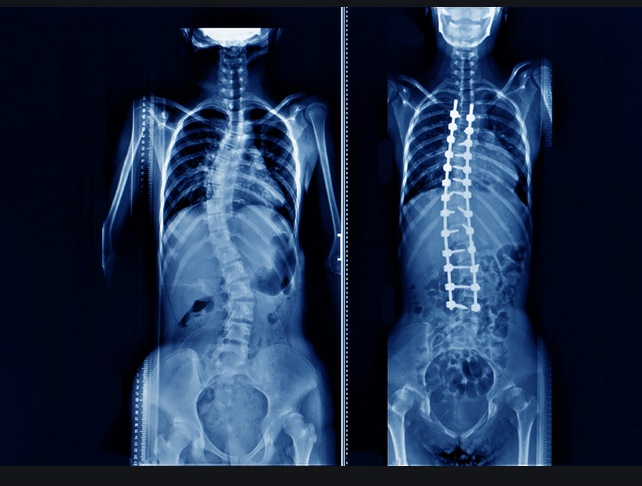

Hab kein röntgenbild vorliegen... Aber es ist eine Fehlstellung sogar mit bloßen Auge zu erkennen.. Wird mir zumindest gesagt ich seh da ja nix ![]()

Die grumme Wirbelsäule hat dann aber nix mit dem Arbeitsunfall zu tun.

Nicht ganz Ronny.. Die Wirbelsäule, hat sich durch den Europaletten Malheur viel weiter verschoben /bzw verbogen..

Resultat... Sitzen nur unter schmerzen

Liegen nur auf den Rücken möglich..